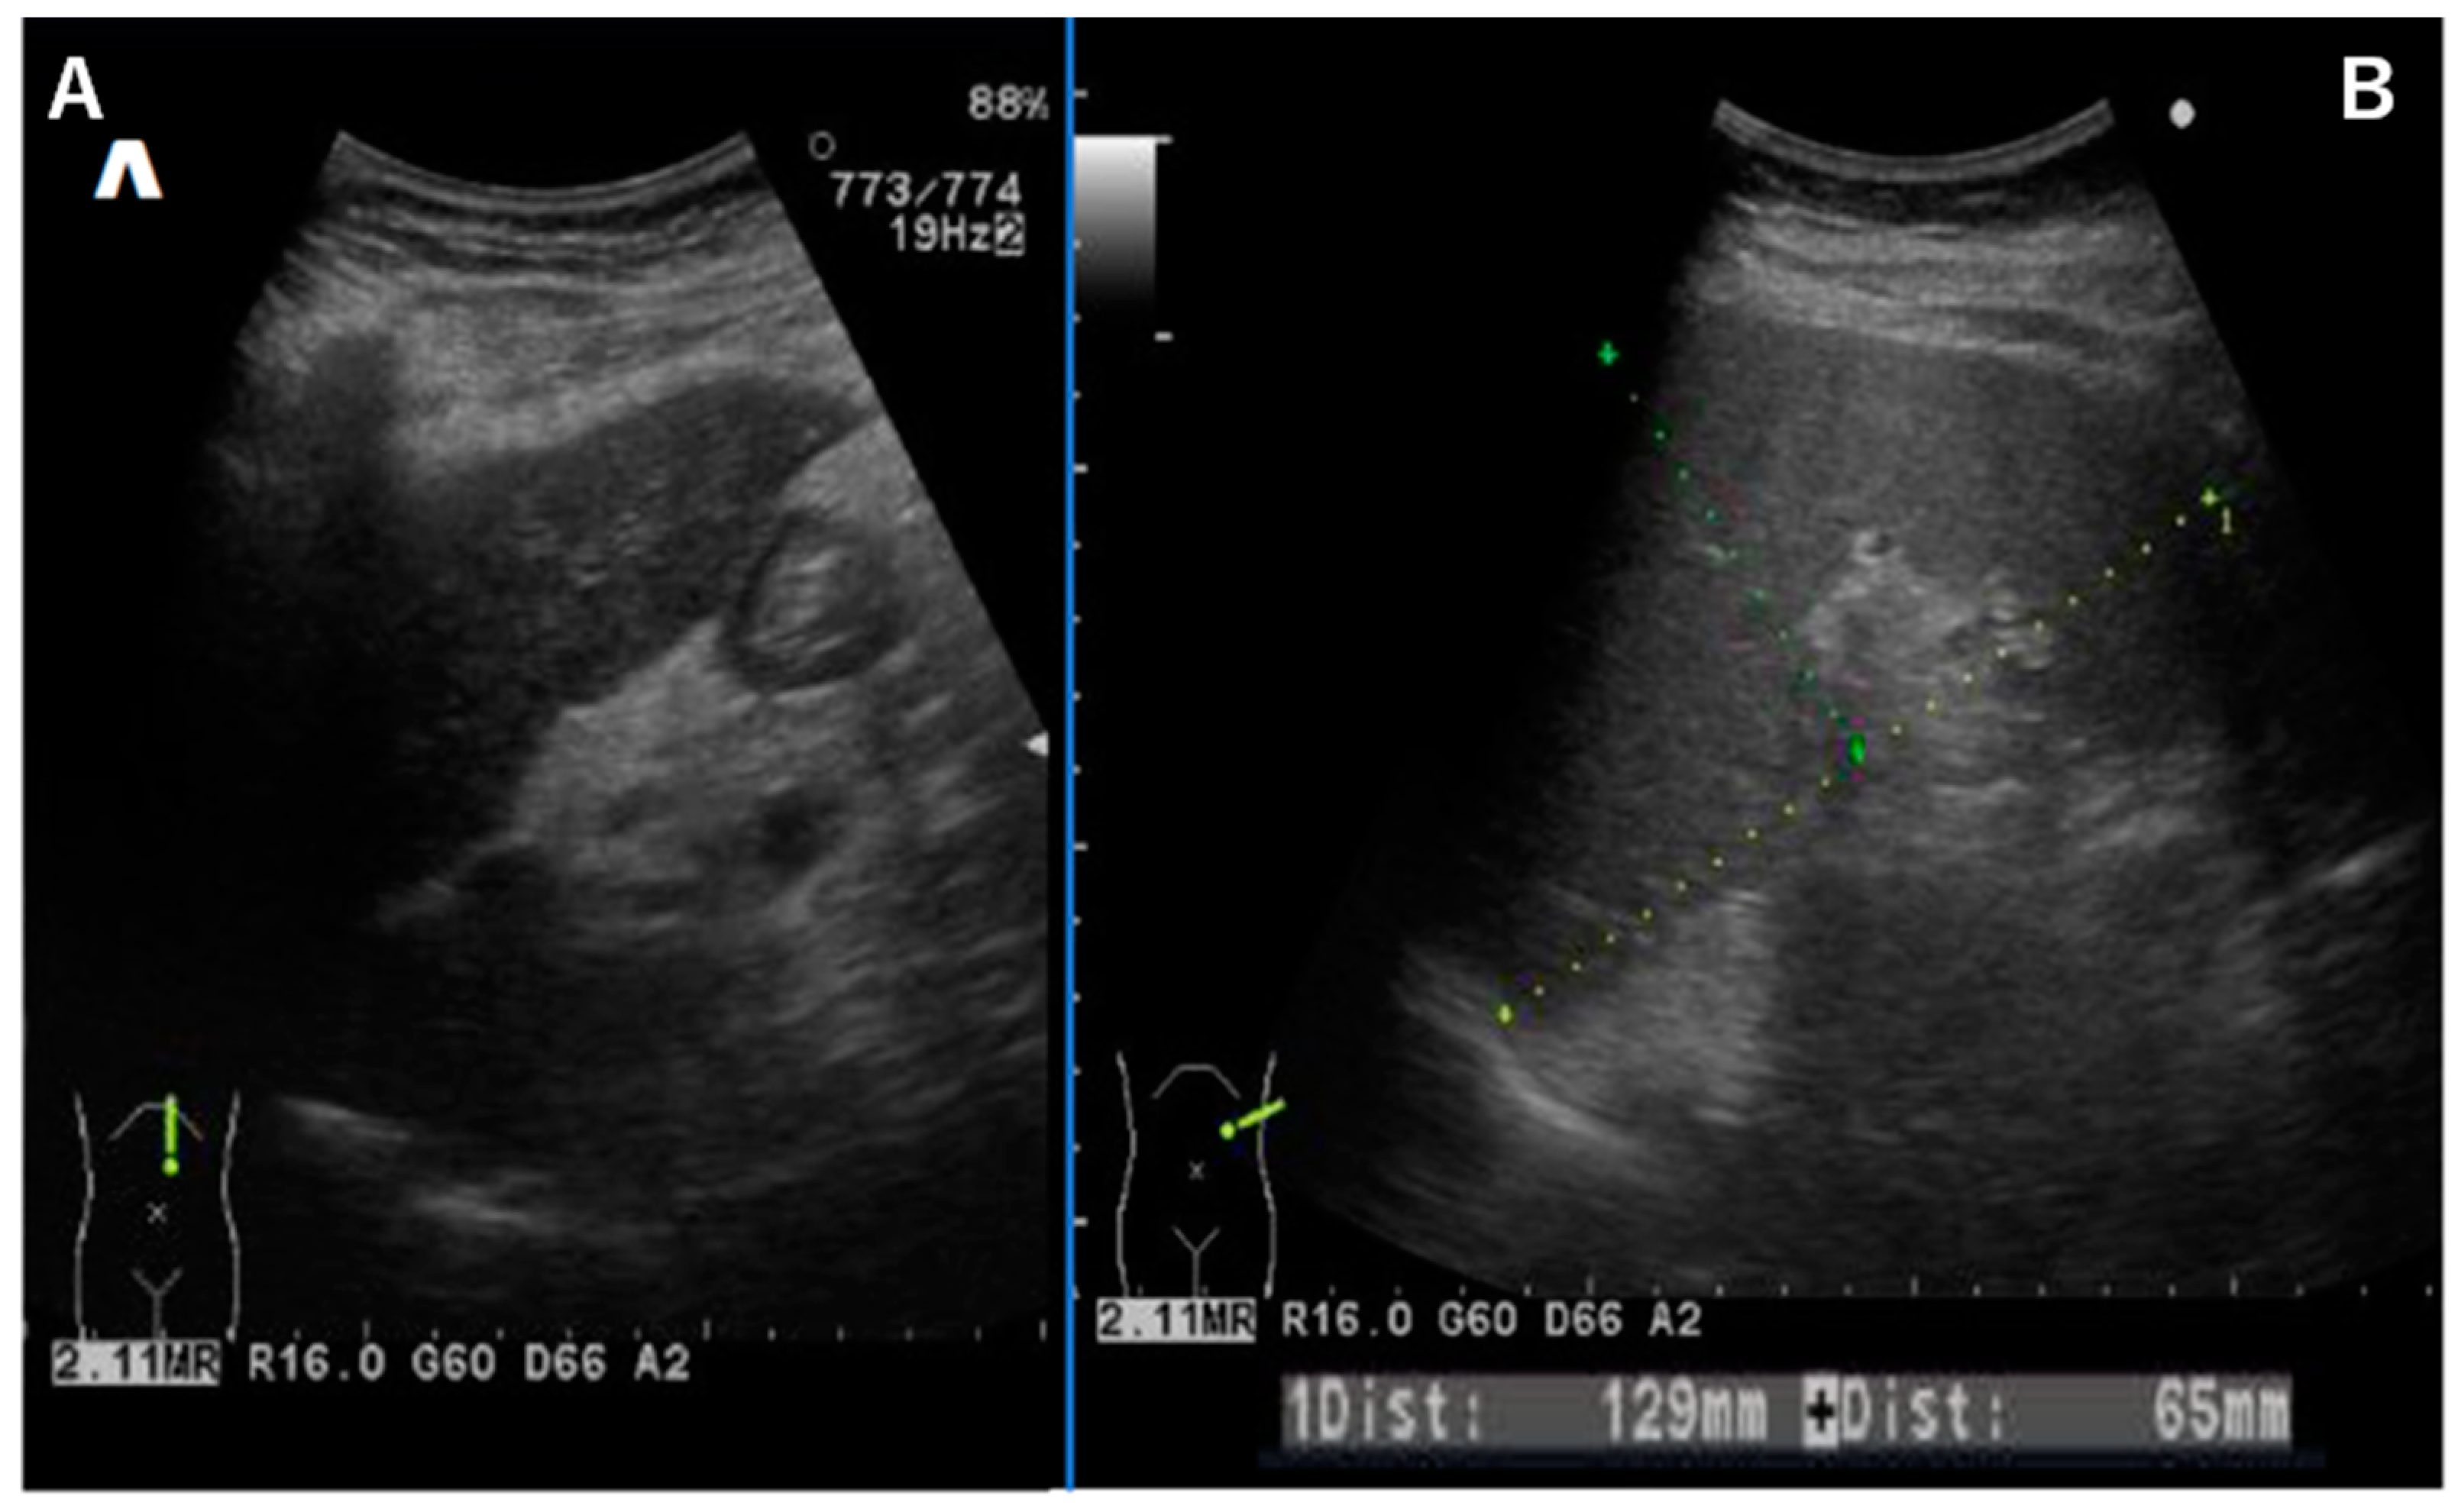

Abdominal ultrasound showed a liver contour with an irregular appearance, consistent with the findings of liver cirrhosis (Figure 2A). The spleen was enlarged, and ascites were absent (Figure 2B). Esophageal varices were thought to be due to portal hypertension. A liver biopsy was not performed because of its associated invasive risks.

Figure 2.

Abdominal ultrasound showing a liver contour with an irregular appearance (A). The spleen was enlarged, and ascites were absent (B).